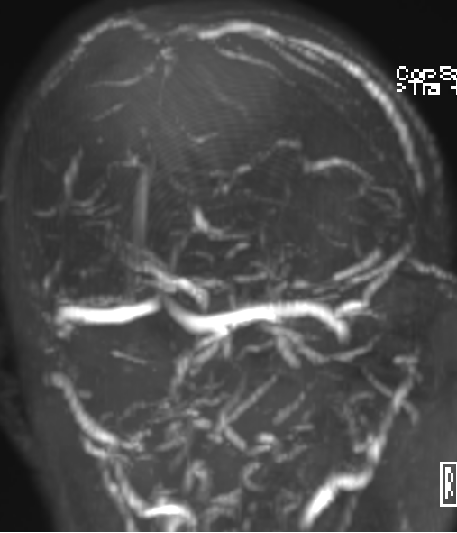

2015-1-30 DSA